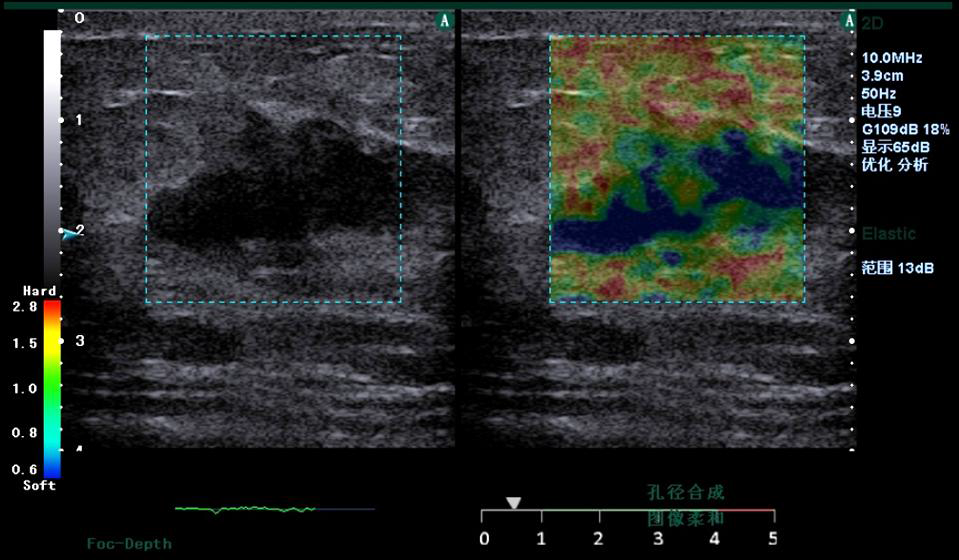

Elasticity Imaging in Healthcare

1. Introduction

Tissue elasticity offers clinically significant information on

tumor and lesion growth, including early state characterization

that may greatly assist early diagnosis. We present

visualization of tissue elasticity through two methods:

1) Freehand elastography using manual probe compression

2) Sound-Push© elastography & shear wave speed

estimation using ARFI

Figure 3. Clinical strain images of confirmed (a) inflammation lesion; (b) benign and (c) malignant breast tumor

2. Freehand elastography

Motion tracking of manual compression or breathing

induced movement generates a strain image

representing the elasticity of the underlying tissue. Statemed